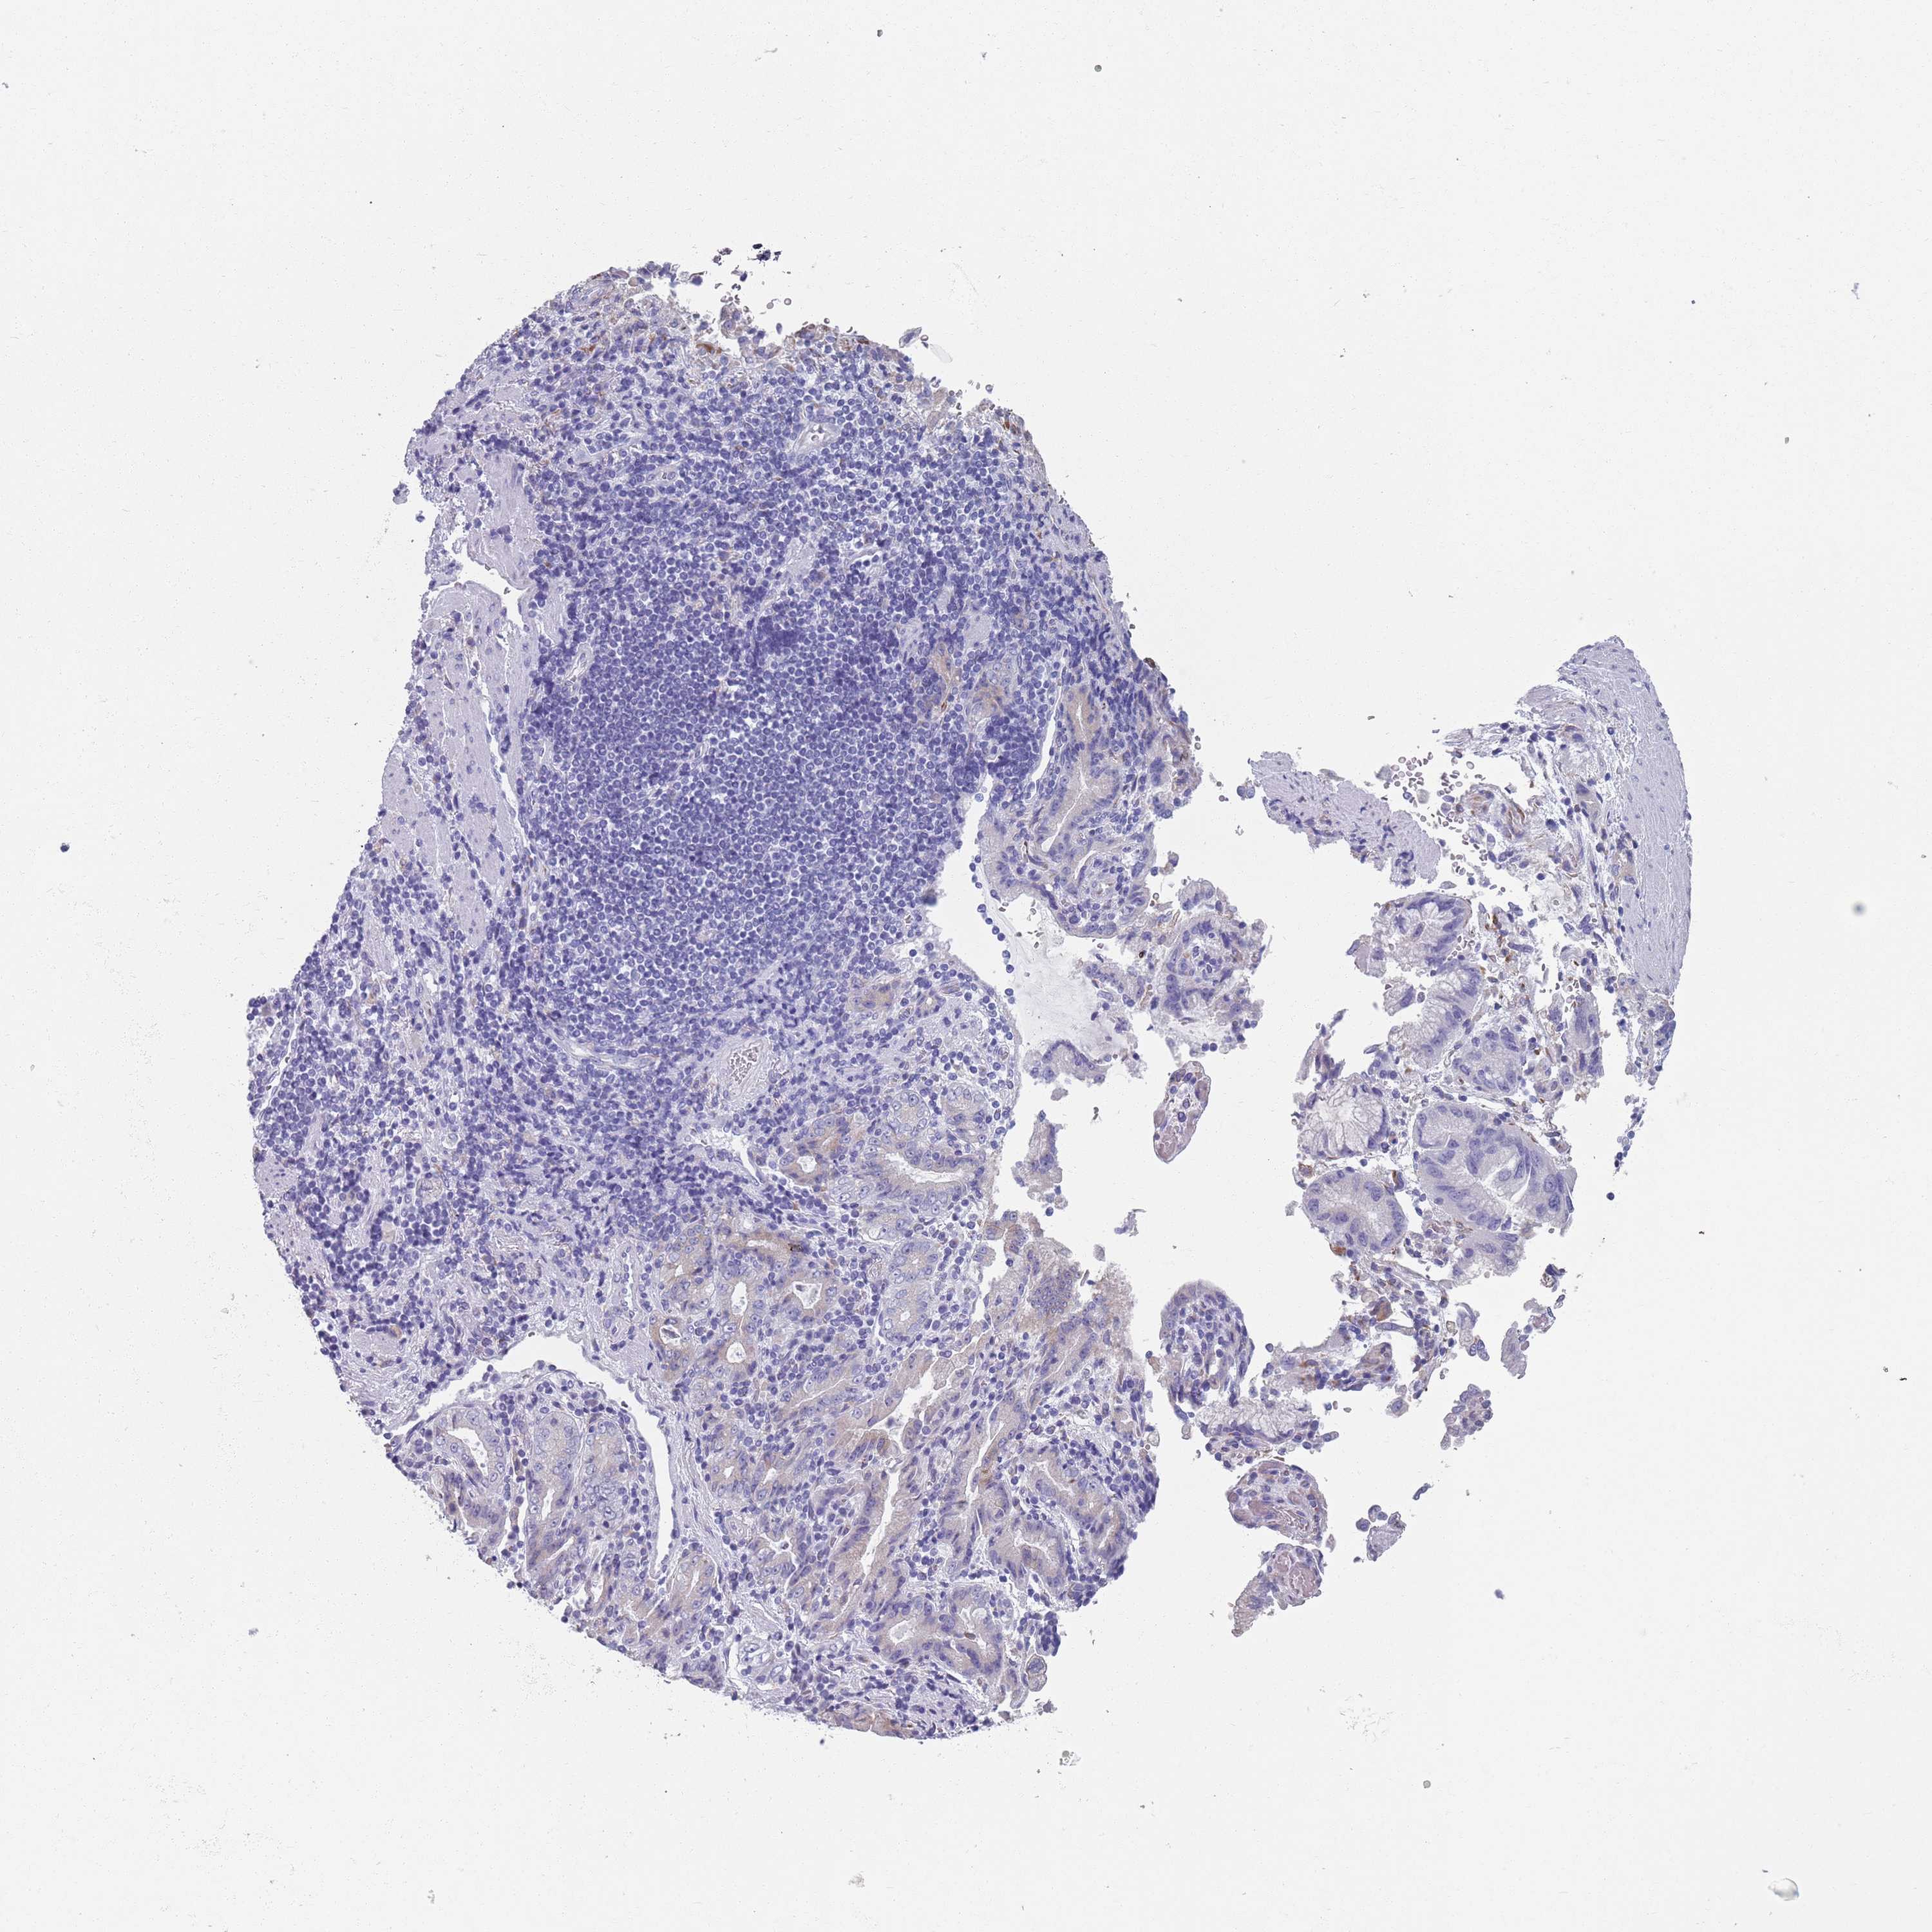

STOMACH CANCER - Protein expressioni

A mouse-over function shows sample information and annotation data. Click on an image to view it in a full screen mode. Samples can be filtered based on level of antibody staining by selecting one or several of the following categories: high, medium, low and not detected. The assay and annotation is described here.

Note that samples used for immunohistochemistry by the Human Protein Atlas do not correspond to samples in the TCGA dataset.

Antibody stainingi

Antibody staining in the annotated cell types in the current human tissue is reported as not detected, low, medium, or high, based on conventional immunohistochemistry profiling in selected tissues. This score is based on the combination of the staining intensity and fraction of stained cells.

Each image is clickable and will lead to virtual microscopy that enables deeper exploration of all samples and also displays staining intensity scores, fraction scores and subcellular localization as well as patient and tissue information for each sample.

Antibody HPA049137

Antibody HPA055799

Staining

High

Medium

Low

Not detected

Intensity

Strong

Moderate

Weak

Negative

Quantity

>75%

75%-25%

<25%

None

Location

Nuclear

Cytoplasmic/membranous

Cytoplasmic/membranous,nuclear

Adenocarcinoma, NOS